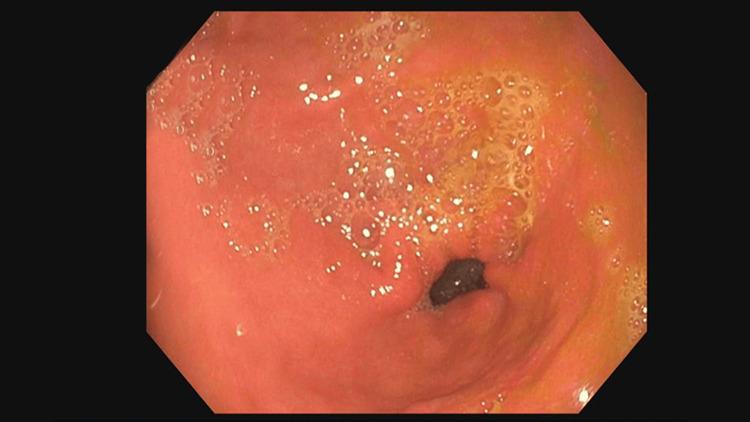

In this case report, we discuss a very rare presentation of a duodenal carcinoid tumor causing a gastric outlet obstruction that was initially misdiagnosed as gastroparesis due to uncontrolled diabetes. This tumor did not present with the usual symptoms or as carcinoid syndrome, as it was negative for all tumor markers and metanephrines. Treatment typically includes preoperative administration of somatostatin analogs, however, these were not used as the tumor showed no evidence of hormone secretion. Early operative treatment is indicated due to the poor prognosis associated with metastatic disease; however, this nonfunctioning tumor, with less than 3% Ki-67 positivity, was classified as low-grade. During esophagogastroduodenoscopy (EGD) and surgical resection, the mass was observed to be highly mobile, intermittently prolapsing retrograde through the pylorus and acting as a one-way valve, obstructing the passage of fluids and food into the duodenum. Consequently, this gastric outlet-like picture was intermittent. The patient's history of uncontrolled diabetes and gastroparesis complicated the diagnosis as each episode of vomiting resolved on its own without any interventions. This made diagnosis of his underlying condition difficult. In this case, we present this rare type of carcinoid obstruction as well as surgical options and surveillance for these tumors.

在本病例报告中,我们讨论了一例极为罕见的十二指肠类癌肿瘤表现,该肿瘤导致胃出口梗阻,最初因糖尿病控制不佳被误诊为胃轻瘫。此肿瘤未表现出常见症状或类癌综合征,因为所有肿瘤标志物和甲氧基肾上腺素均为阴性。治疗通常包括术前使用生长抑素类似物,然而,由于肿瘤未显示激素分泌证据,未使用这些药物。鉴于转移性疾病预后较差,应尽早进行手术治疗;然而,此无功能肿瘤的Ki-67阳性率低于3%,被归类为低级别。在食管胃十二指肠镜检查(EGD)和手术切除过程中,观察到肿块活动度极高,间歇性地逆行通过幽门突出,起到单向瓣膜的作用,阻碍液体和食物进入十二指肠。因此,这种类似胃出口梗阻的情况是间歇性的。患者未控制的糖尿病和胃轻瘫病史使诊断复杂化,因为每次呕吐发作均自行缓解,无需任何干预。这使得对其潜在病情的诊断变得困难。在此病例中,我们展示了这种罕见类型的类癌梗阻以及针对这些肿瘤的手术选择和监测。